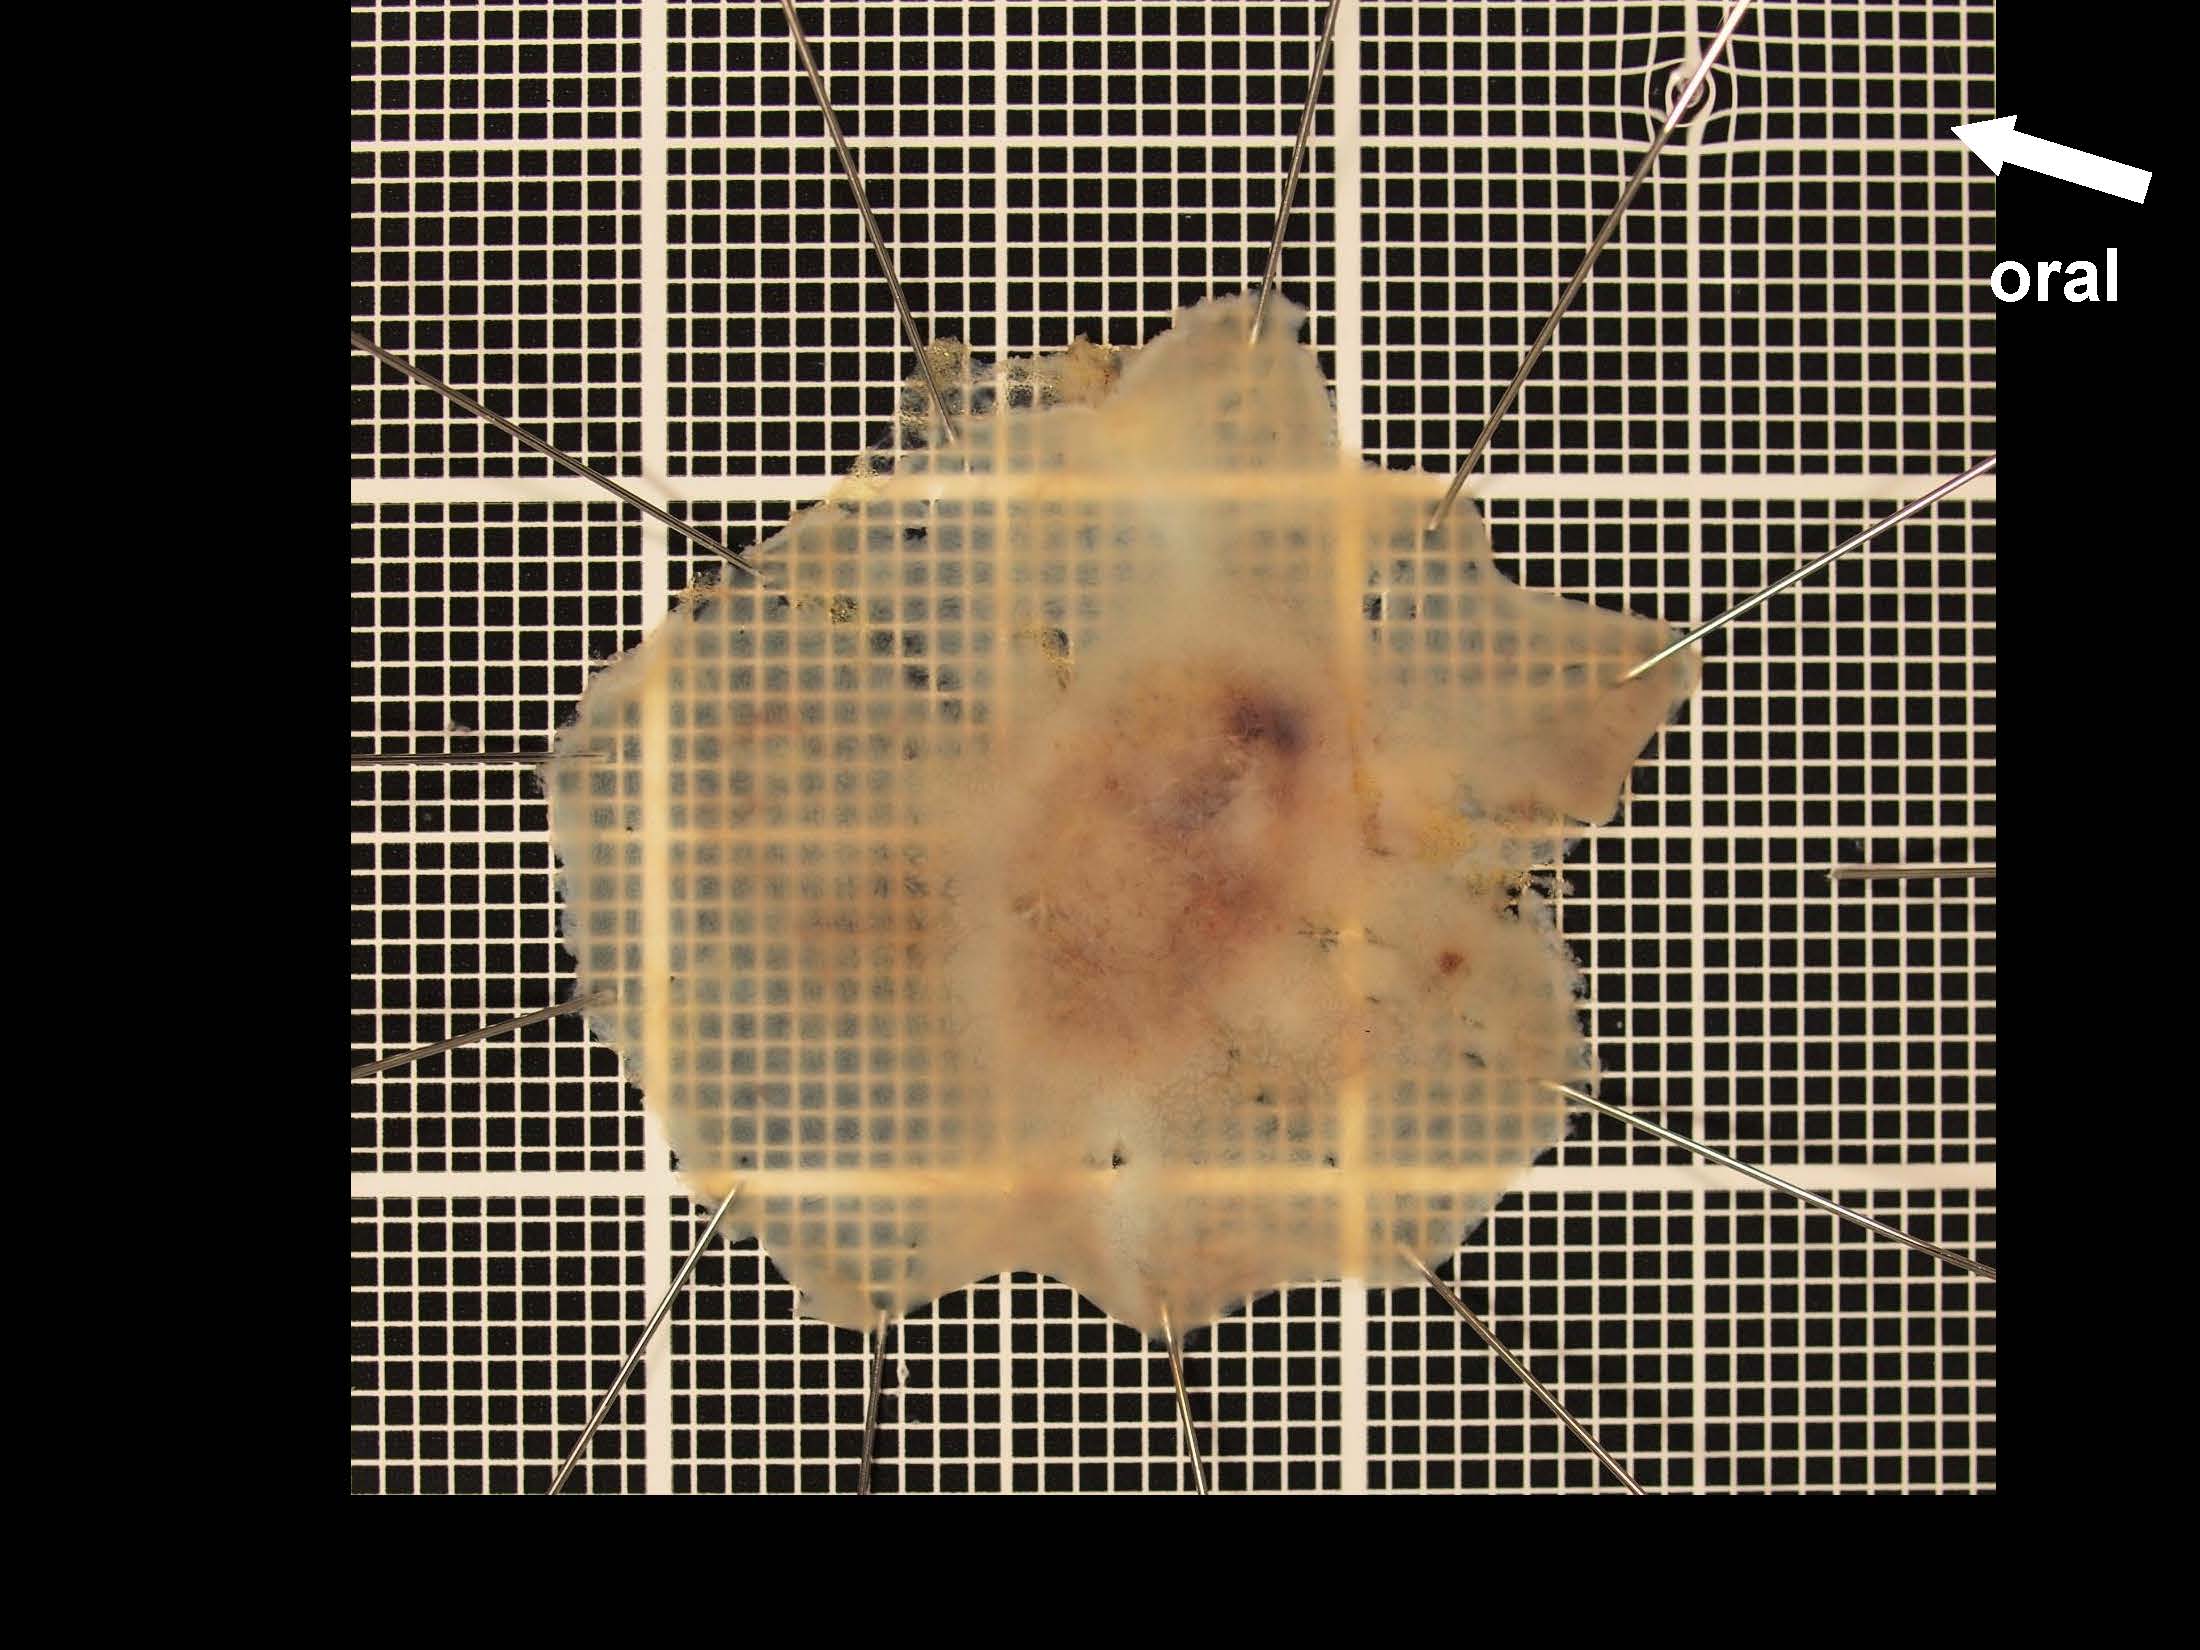

消化管Mapping~大腸~ 2021.10.27

消化器センター 消化器内科

消化管Mapping

消化管Mapping~大腸~

内視鏡検査・治療